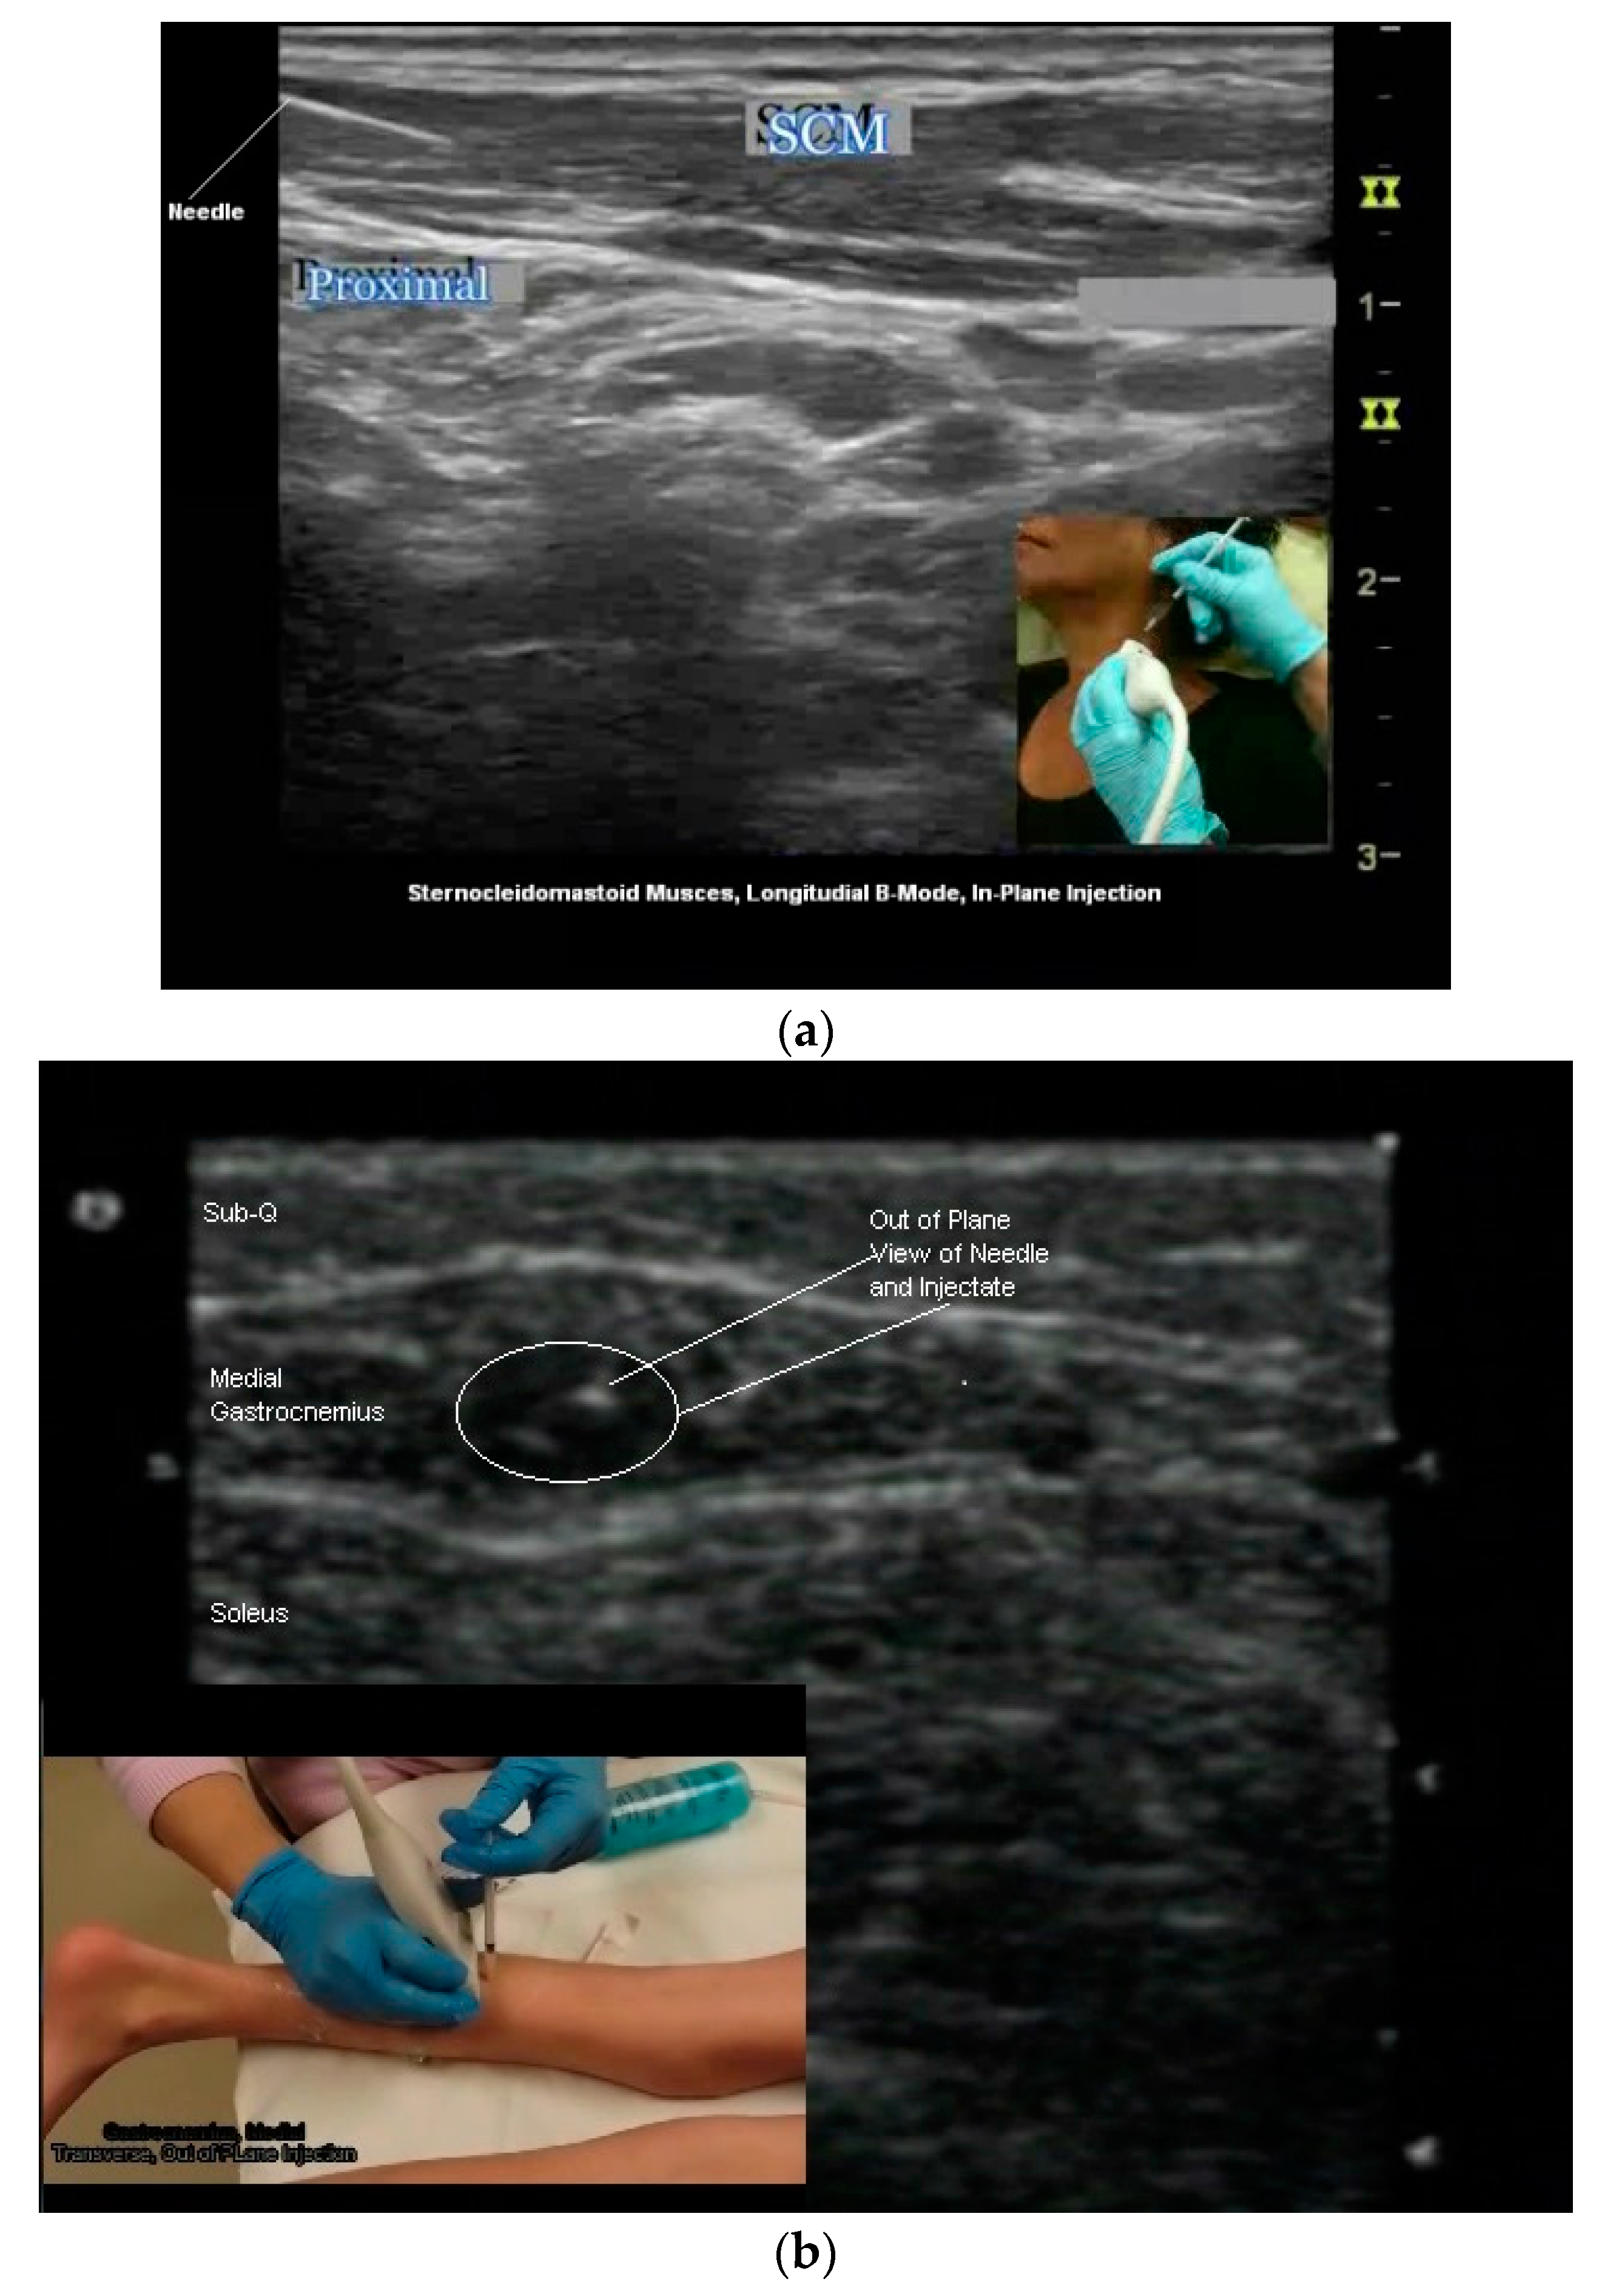

(a) Longitudinal B-mode US image, inplane injection; (b) transverse B-mode US image, out of plane injection medial gastrocnemius; (c) illustration, out of plane view of needle tip and shaft.

Two needle insertion techniques are utilized when performing US guided BoNT injections: Out of plane and in plane (Figure 6b,c and Figure 7a–c). There are advantages and limitations to each insertion technique. One technique may be superior to the other for a given patient or particular muscle/structure. Therefore clinicians should be familiar with both approaches [24,50,54].

- In Plane Technique (IPT). When using an IPT the needle is inserted along the length of the transducer (Figure 6b and Figure 7a). With the IPT, the entire needle and its tip is visualized, an advantage over the OPT. However, this technique can be challenging to perform because the sonographer must keep the needle within the narrow US beam. Another challenge is that optimal needle visualization requires that the needle be inserted and maintained in an orientation perpendicular to the US beam Figure 8a. When inserted at a steep or oblique angle, visualization of the needle may be lost due to needle anisotropy [24,50,54] (Figure 8b).